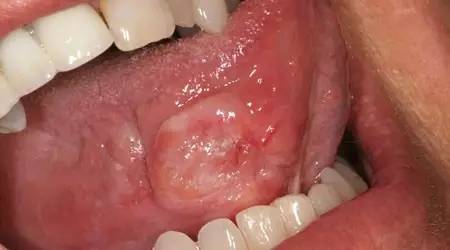

9、口腔溃疡

口腔溃疡是出现在嘴唇、喉后或舌底的小的、白色或灰色的溃疡,边缘红色。溃疡的确切病因不清楚,有些人认为,免疫系统问题、细菌或病毒可能起作用。女性更易发生口腔溃疡。

口腔溃疡没有传染性,通常1~2周后自愈。非处方药膏和漱口水可以暂时缓解。在痊愈前,远离热、辛辣或酸性的食物,因为这些可能会刺激溃疡。

10、癌症

每年大约有40000例确诊的口腔癌、喉癌、扁桃体或舌根部癌症新发病例。吸烟、酗酒和人乳头瘤病毒(HPV)感染都会增加患癌风险。男性患口腔癌的风险比女性高两倍。

在定期检查时,医生会检查口腔中有没有红色或白色斑块、无法痊愈的溃疡以及粗糙、硬实的斑点。如果有任何可疑症状,口腔医生可能会进行更多测试或推荐专科治疗。上面这张图只是口腔癌可能的一种表现。